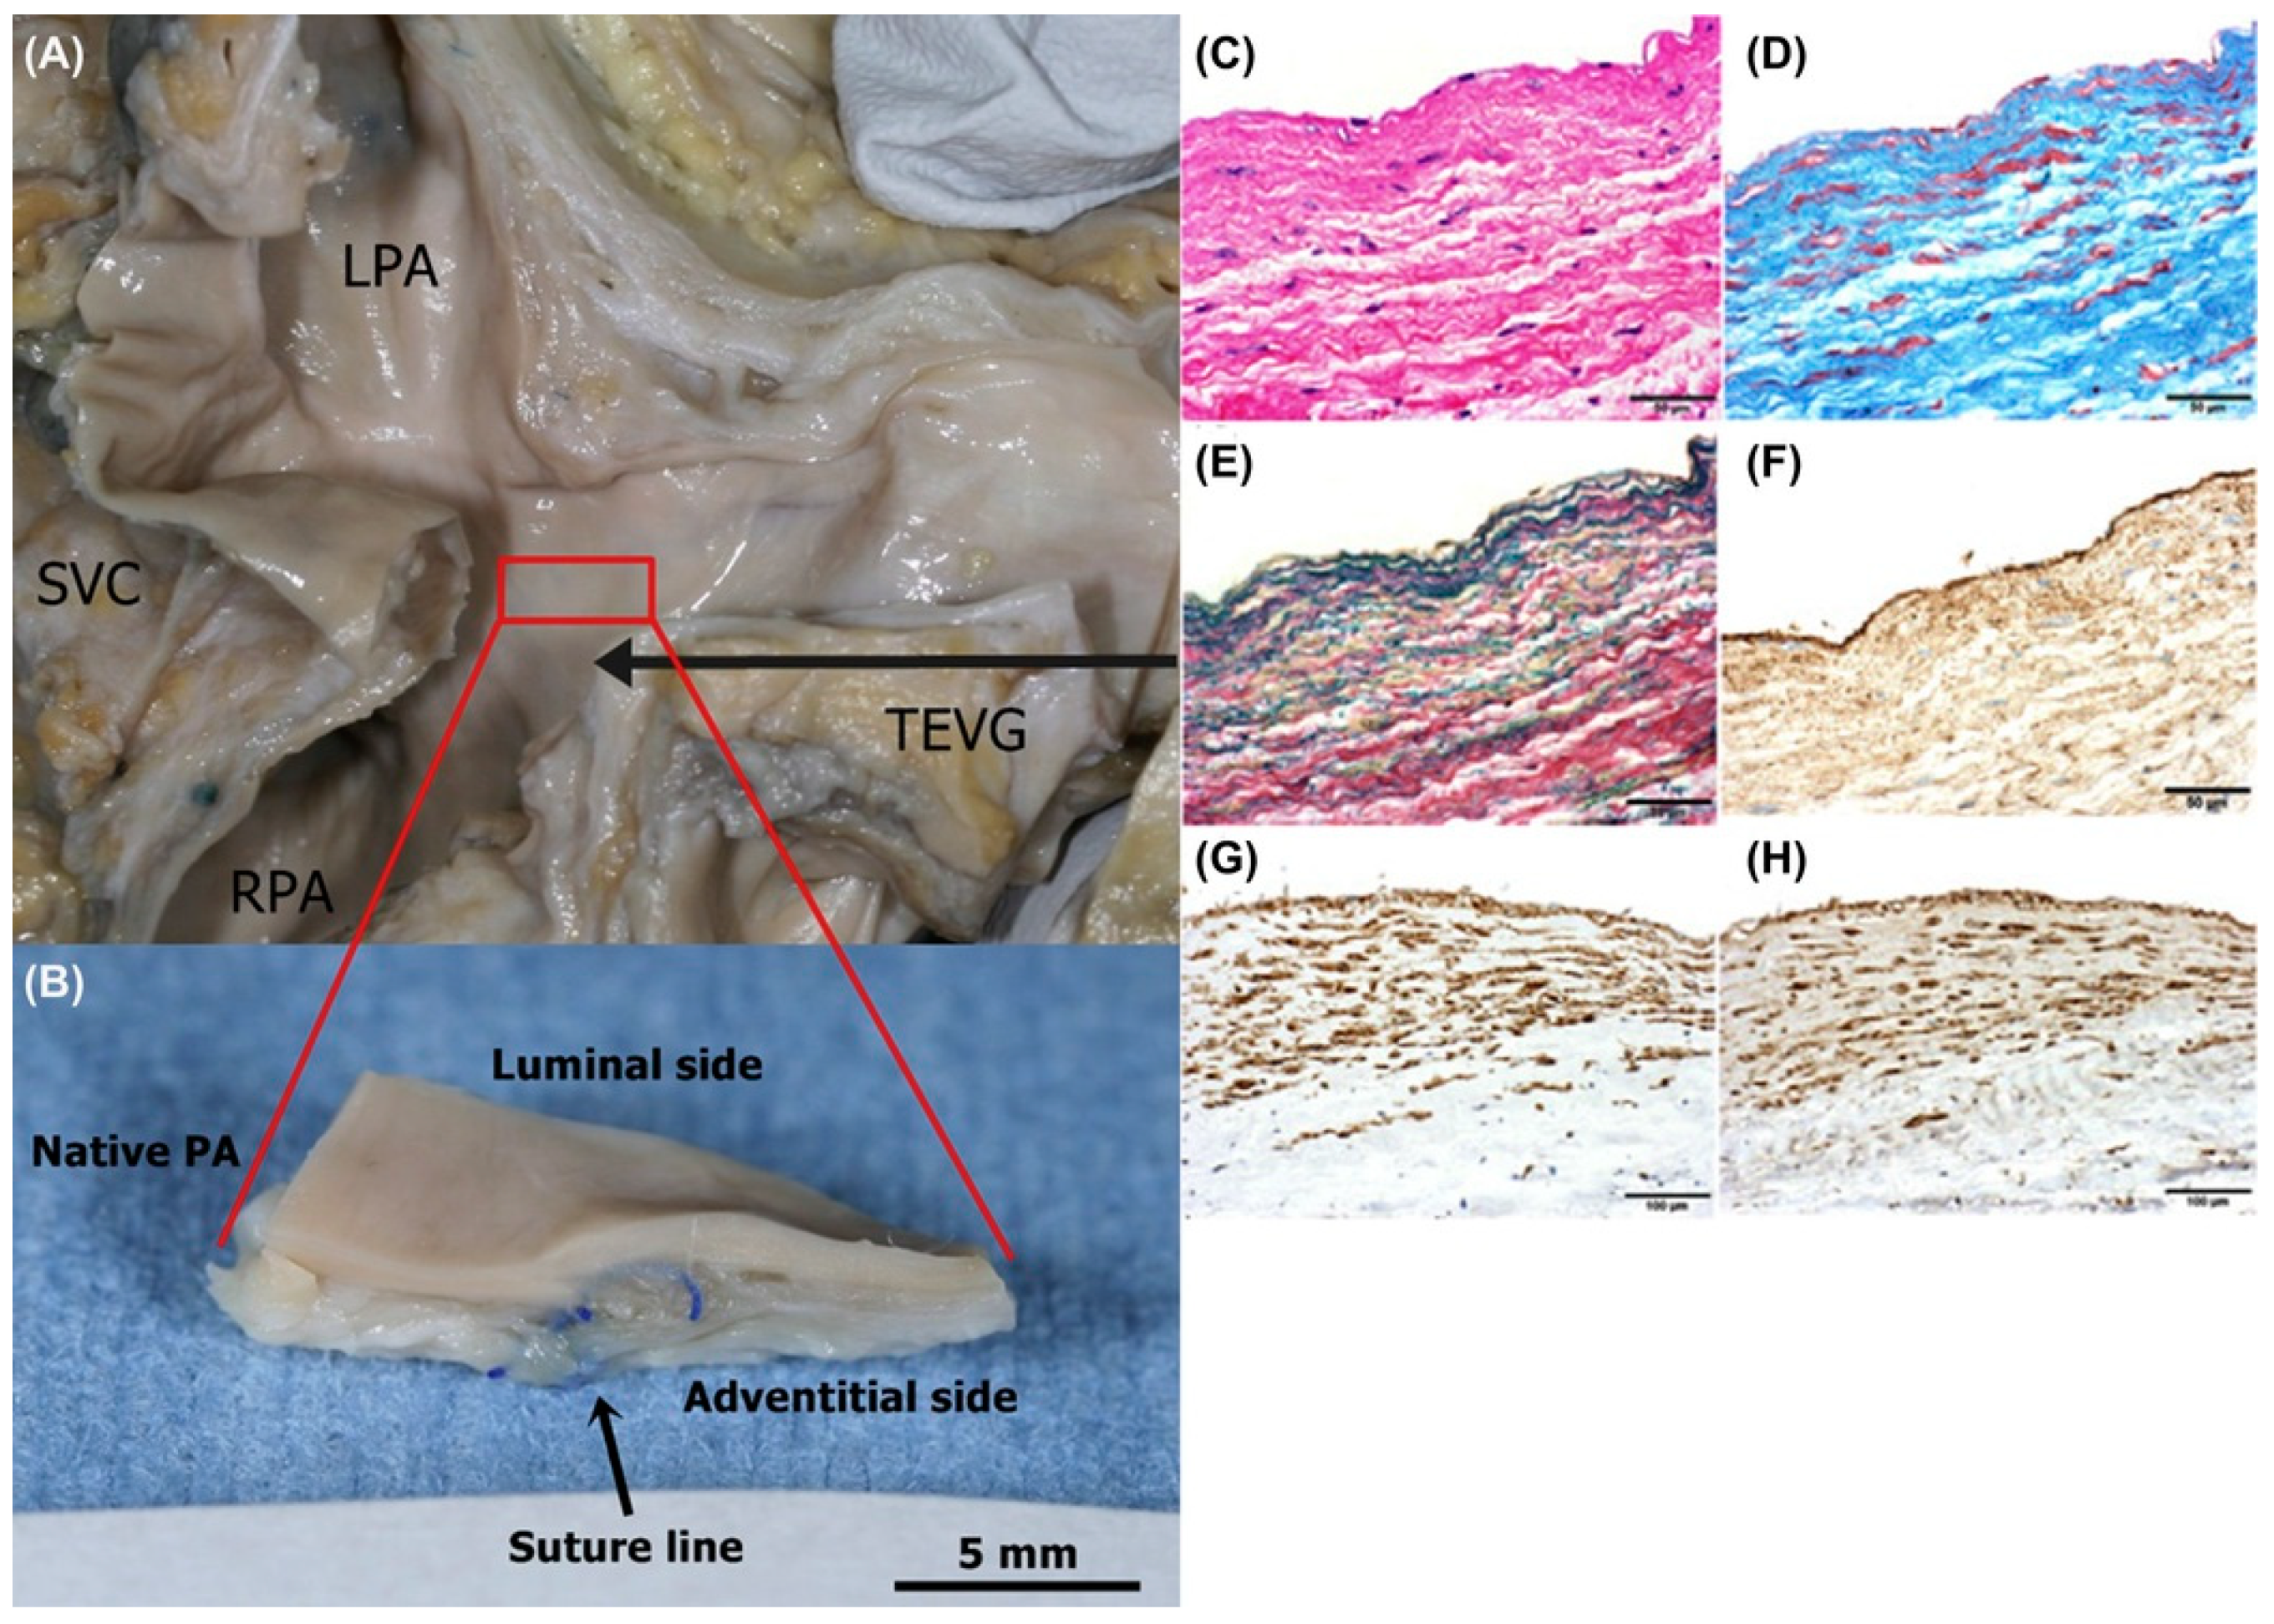

3. Clinical Study in Venous Model

- Shinoka, T.; Imai, Y.; Ikada, Y. Transplantation of a tissue-engineered pulmonary artery. N. Engl. J. Med. 2001, 344, 532–533. [Google Scholar] [CrossRef] [PubMed]

- Shinoka, T.; Matsumura, G.; Hibino, N.; Naito, Y.; Watanabe, W.; Konuma, T.; Sakamoto, T.; Nagatsu, M.; Kurosawa, H. Midterm clinical result of tissue-engineered vascular autografts seeded with autologous bone marrow cells. J. Thorac. Cardiovasc. Surg. 2005, 129, 1330–1338. [Google Scholar] [CrossRef] [PubMed] [Green Version]

- Hibino, N.; McGillicuddy, E.; Matsumura, G.; Ichihara, Y.; Naito, Y.; Breuer, C.K.; Shinoka, T. Late-term results of tissue- engineered vascular grafts in humans. J. Thorac. Cardiovasc. Surg. 2010, 139, 431–436. [Google Scholar] [CrossRef] [PubMed]

- Sugiura, T.; Matsumura, G.; Miyamoto, S.; Miyachi, H.; Breuer, C.K.; Shinoka, T. Tissue-engineered Vascular Grafts in Children With Congenital Heart Disease: Intermediate Term Follow-up. Semin. Thoracic. Surg. 2018, 30, 175–179. [Google Scholar] [CrossRef] [PubMed]

- Brennan, M.P.; Dardik, A.; Hibino, N.; Roh, J.D.; Nelson, G.N.; Papademitris, X.; SHinoka, T.; Breure, C.K. Tissue-engineered vascular grafts demonstrate evidence of growth and development when implanted in a juvenile animal model. Ann. Surg. 2008, 248, 370–377. [Google Scholar] [CrossRef]